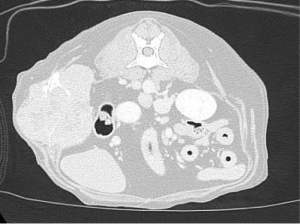

今回は左最後肋骨の中央に発生しており、かつ体壁の内側に成長していたために発見が遅れたと推測されます。サイズはφ10cm大で皮膚への固着はありませんでした。CTでは、肺野の転移像はなく脊椎への浸潤も確認されませんでした。

CTより肋骨から派生した腫瘍が疑われました。CTでも明らかな肺転移は確認されませんでした。